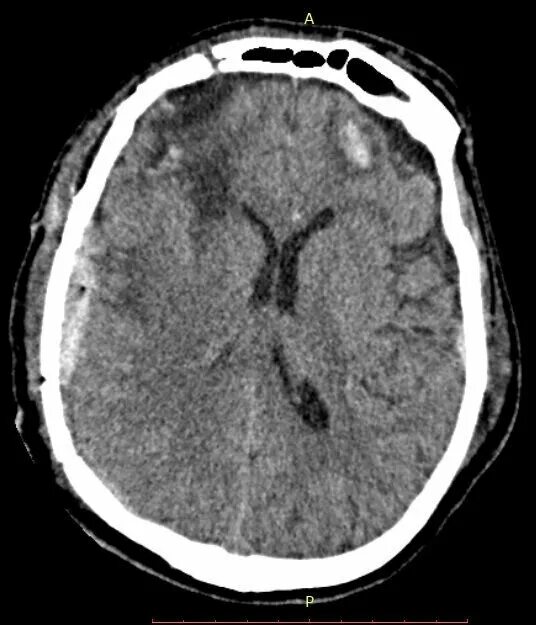

Гематома лобной